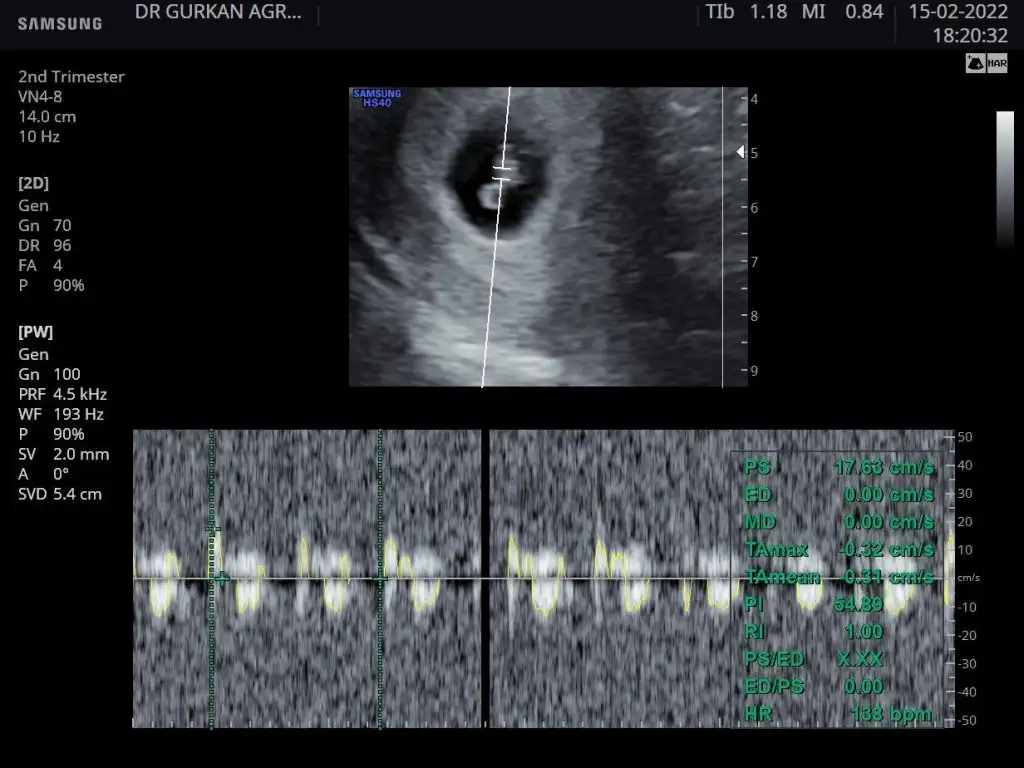

kız gibi duruyor canımHayırlı geceler kızlar14+1 ken doktorum%80 kız demişti sizde bakar mısınız sonuç degismz demi kızım olsun istiyorum